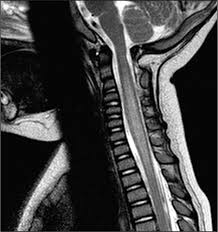

Transverse Myelitis Radiology / Transverse Myelitis Evolution In Mri Radiology Case Radiopaedia Org / G37.3 acute transverse myelitis in demyelinating disease of central nervous system g37.4 subacute necrotizing myelitis of central nervous system g37.5 concentric sclerosis balo of central nervous system g37.8 other specified demyelinating diseases of central nervous system g37.9 demyelinating disease of central nervous system, unspecified. The av shunt is located inside the dura mater close to the spinal nerve root where the arterial blood from a. Jan 14, 2017 · transverse myelitis is an inflammatory condition of the spinal cord associated with rapidly progressive neurologic dysfunction. Rare neurological complications include transverse myelitis and/or cauda equina syndrome 20, 21; In the acute setting, there is often associated contrast enhancement. G37.3 acute transverse myelitis in demyelinating disease of central nervous system g37.4 subacute necrotizing myelitis of central nervous system g37.5 concentric sclerosis balo of central nervous system g37.8 other specified demyelinating diseases of central nervous system g37.9 demyelinating disease of central nervous system, unspecified

Jan 14, 2017 · transverse myelitis is an inflammatory condition of the spinal cord associated with rapidly progressive neurologic dysfunction.